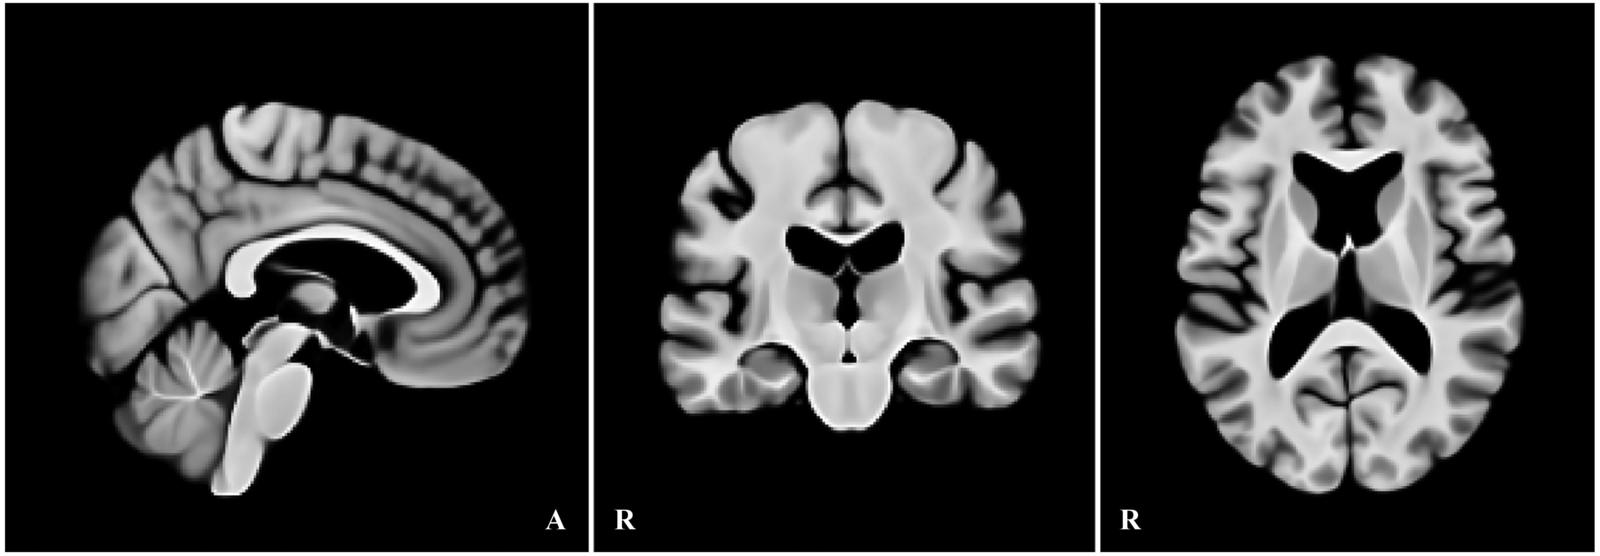

本研究では、加齢に伴う形態変化――特に拡大した側脳室や皮質の萎縮――を前提に、高齢者の脳画像を適切に基準化できる高齢者向け標準脳テンプレートを作成しました。2020年国勢調査に基づく日本の高齢者の男女比と年齢分布を考慮し、標準脳の構成が実情を反映するよう設計しています。作成データとしてOASIS-1の高齢者90例、検証データにはIXIの282例を用い、従来広く用いられているMNI152と比較しました。

検証では、IXIの各画像データを上記の手順で作成した高齢者向けテンプレートとMNI152の双方に同条件で登録し、全脳の整合(CC/MSE)と皮質下の領域(尾状核・海馬・視床・扁桃体)の一致度(Dice係数)を評価しました。その結果、60歳以降で整合が明確に向上し、CCは上昇、MSEは低下しました。特に、拡大した側脳室の位置合わせが安定し、加齢に伴う形態をより正しく反映できることが示されました。さらに、皮質下の各領域ではDice係数が1~4%向上し、局所の位置合わせ精度も改善しました。